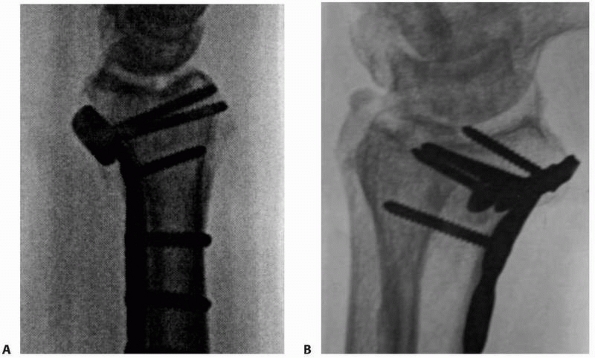

![]() |

|

FIGURE 30-17 A-C. Comminuted radius fracture in a poly trauma patient treated with percutaneous pinning technique.

FIGURE 30-21 Technique of percutaneous pinning of a dorsally comminuted metaphyseal fracture (A).

First the palmar cortex is re-approximated percutaneously using a curved Hohman retractor through an incision dorsally in the interval between the third and fourth dorsal compartments (B,C). The palmar tilt is restored and held with the fixator (D) and the subsequent metaphyseal defect is grafted using cancellous allograft (E). (continues) |

FIGURE 30-21 (continued) Finally, the lateral cortex is reduced with a percutaneously applied tenaculum clamp and crossed pins are inserted (F-H). The stability of the construct may be improved with the use of an additional pin applied radially (I).